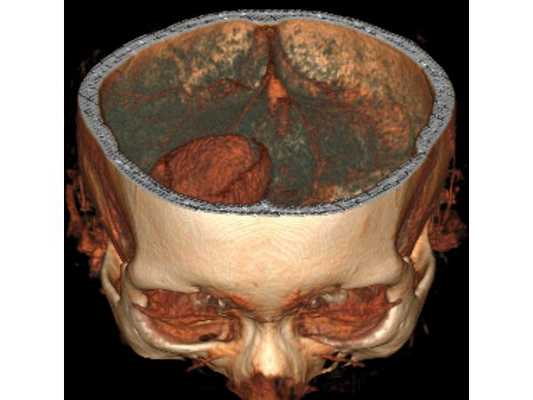

3D-реконструкция объёмного образования правой лобной доли головного мозга, выполненная на основании сканов КТ с контрастным усилением

На основании диагноза проведена краниотомия (трепанация черепа) и удаление абсцесса правой лобной доли: ⠀• выполнен дугообразный разрез мягких тканей в правой лобно-височной области; ⠀• наложено фрезевое отверстие у основания скулового отростка лобной кости, из которого краниотомом выпилен костный лоскут 6*5 см; ⠀• для остановки кровотечения использован хирургический воск и электрокоагуляция по ходу доступа; ⠀• произведено подковообразное вскрытие твёрдой мозговой оболочки основанием к сагиттальному синусу: абсцесс был хорошо отграничен капсулой и подпаянной к коре головного мозга твёрдой мозговой оболочкой; ⠀• тонким шпателем твёрдая мозговая оболочка постепенно отделена от коры, абсцесс вскрыт — получен гной, внешне напоминающий сливки, с гнилостным запахом; ⠀• аспирировано (удалено) около 60 мл гноя; ⠀• полость абсцесса многократно промыта водными растворами перекиси водорода и фурацилина, мозг запал, имеется хорошая пульсация; ⠀• твёрдая мозговая оболочка ушита, по периметру подшито трепанационное окно, костный лоскут уложен на место, на рану наложены послойные швы и асептическая повязка. При оперативных вмешательствах по поводу абсцесса головного мозга принято оставлять дренаж в полости абсцесса. Однако, с учётом наличия хорошо сформированной капсулы, которая была визуализирована после промывания полости антисептическими растворами, принято решение не оставлять дренаж.

Представленный клинический случай может быть рассмотрен как возможный вариант хирургической тактики при хорошо отграниченном абсцессе. Так, аспирация гнойного содержимого абсцесса без удаления капсулы и без дренирования её с последующей антибактериальной терапией, в подобных случаях является достаточным. Единственное, что стоило бы добавить к тактике обследования подобного абсцесса — выполнение перед операцией диагностической люмбальной пункции.